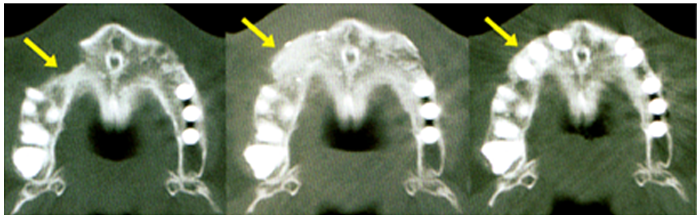

CTにより確実に骨が再生されていることを確認した。

STEP5:骨の確認(CT、レントゲン)を行い、インプラント施術